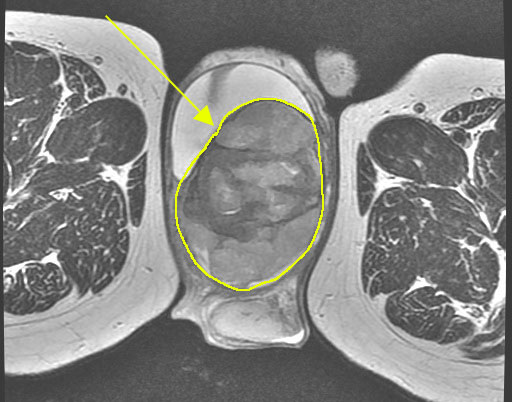

⑤ MRI検査

精巣の形態、内部構造などの情報が得られます。

※精巣がんのMRI画像